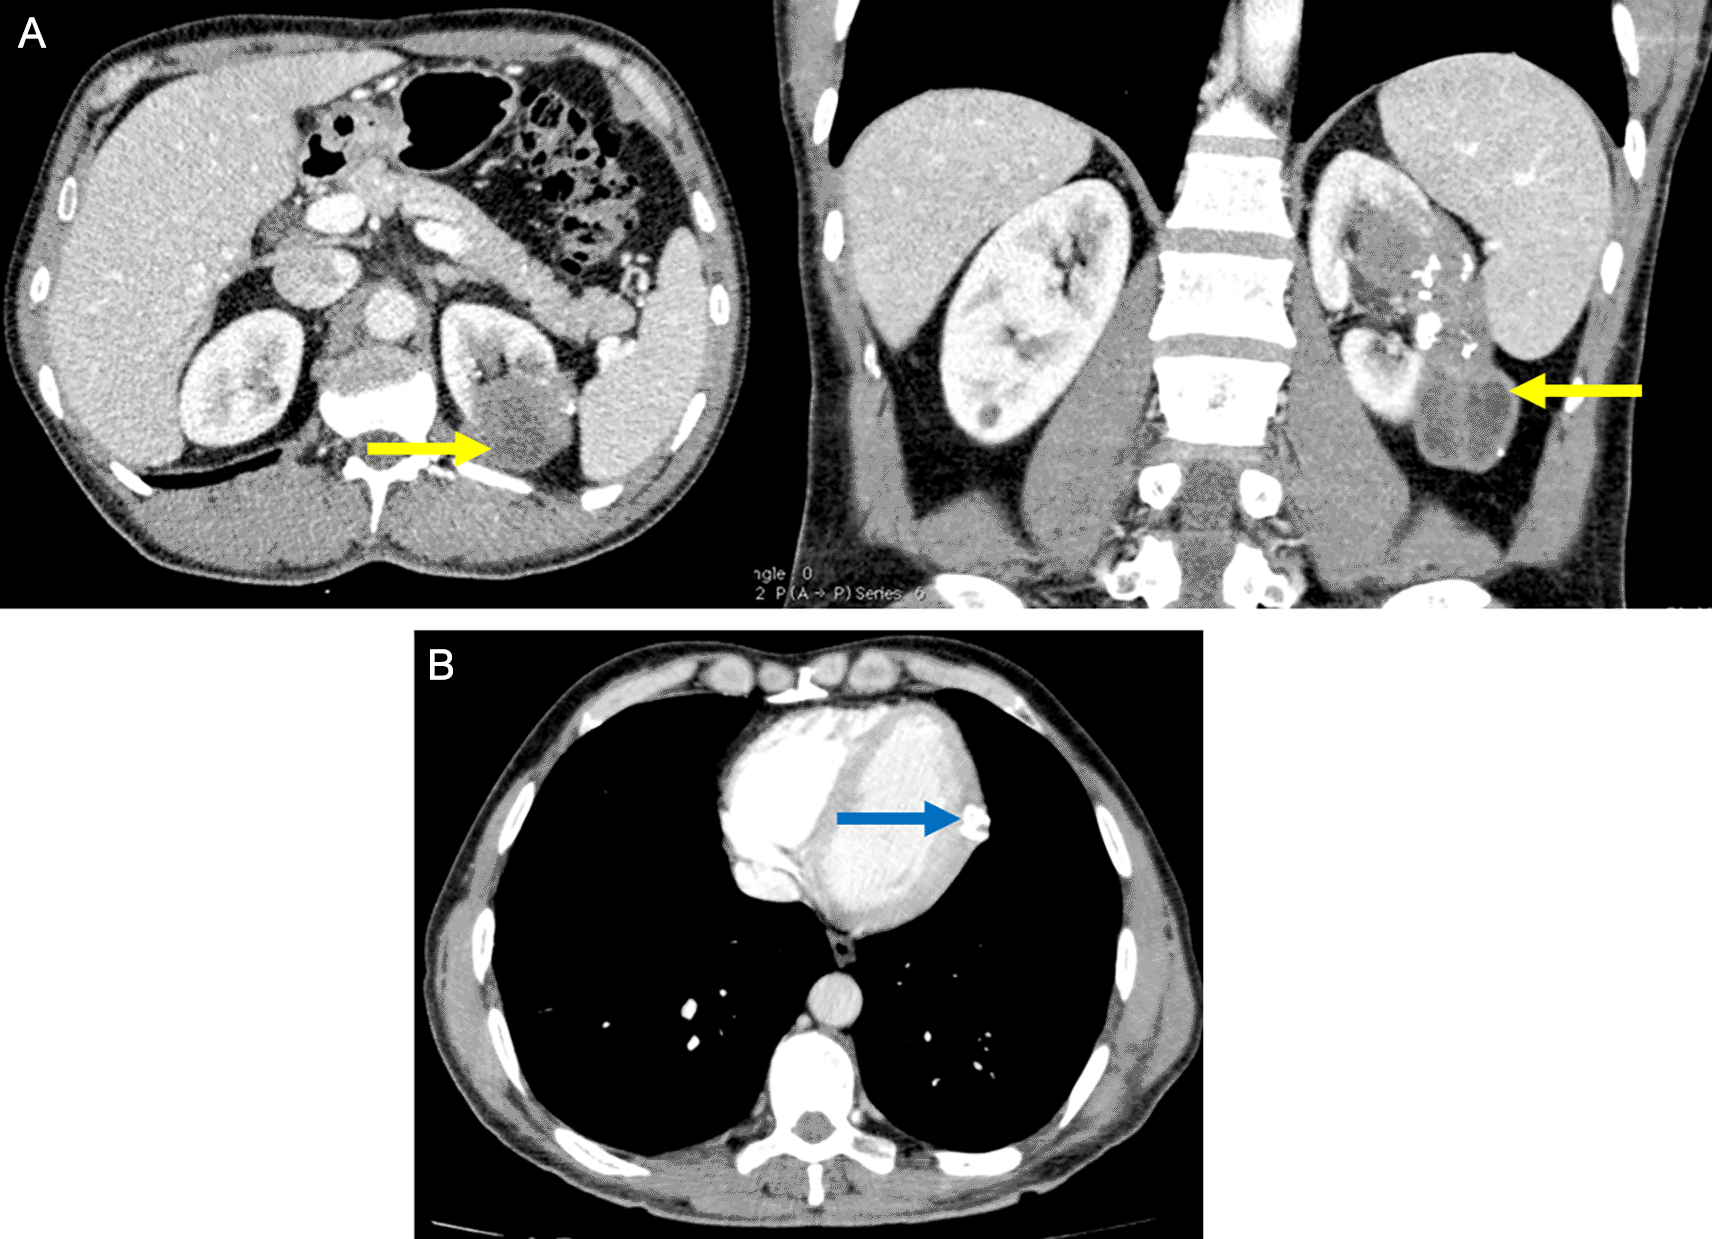

The patient was followed up at the department of abdominal surgery for a multiple organ hydatidosis including 13 hydatid cysts: the lungs, the liver ( Figure 1), the left heart ventricle, the left kidney (Figure 2), the abdomen cavity, the muscles (psoas, adductors), and the subcutaneous gluteal area. Those cysts were already treated surgically (Table 1). The patient has received oral Albendazole 400 mg twice-daily for 2 years.

Renal involvement is also rare (2–3%) and it is usually associated with disseminated disease, they are most commonly asymptomatic, as reported in the present case. The diagnosis was made by an abdominal CT scan which has a sensitivity of 98% in diagnosing hydatid disease.7

Psoas cysts are also uncommon.8 The patient presented with two psoas cysts, a finding that has never been reported in the literature.

The patient has also presented with a 30-mm gluteal subcutaneous cyst, this involvement was described in rare cases in the literature. Patients usually have a painless palpable mass of at least 3 months, and it is usually larger than 3 cm, as it is reported in the present case.9 Subcutaneous cysts tend to involve the trunk and the limb roots, possibly due to the rich vascularization and the relatively lower activity of the muscle in these areas.10